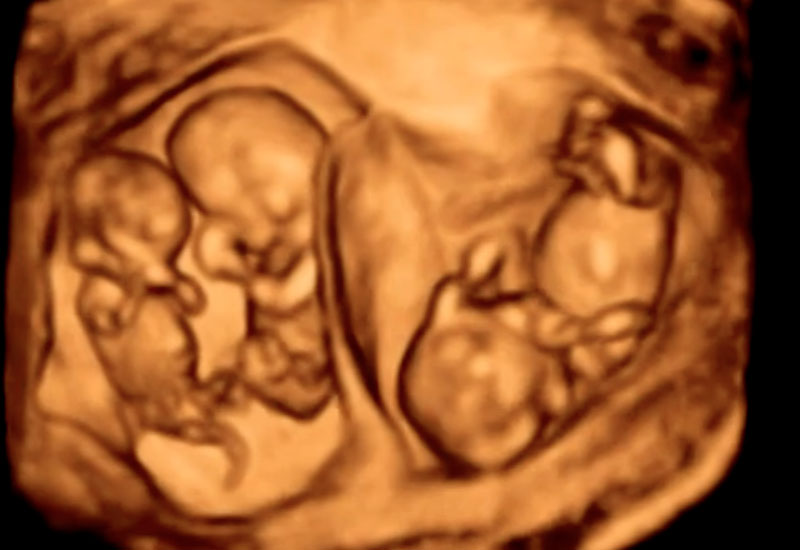

Specialized Twin & Higher-Order Pregnancy Scanning

Twin and higher-order pregnancies require specialized monitoring due to their increased medical complexity and higher risk of complications. Under the expert care of Dr. Ashwini Rathi, advanced ultrasound protocols are used to closely monitor fetal growth, placental sharing, and well-being throughout pregnancy to ensure optimal outcomes for both mother and babies.

Multiple pregnancies carry a higher risk of complications such as preterm birth, fetal growth restriction, pre-eclampsia, and placental abnormalities. In monochorionic twins, additional risks include Twin-to-Twin Transfusion Syndrome (TTTS) and selective growth restriction.

- Confirmation of chorionicity and amnionicity in early pregnancy